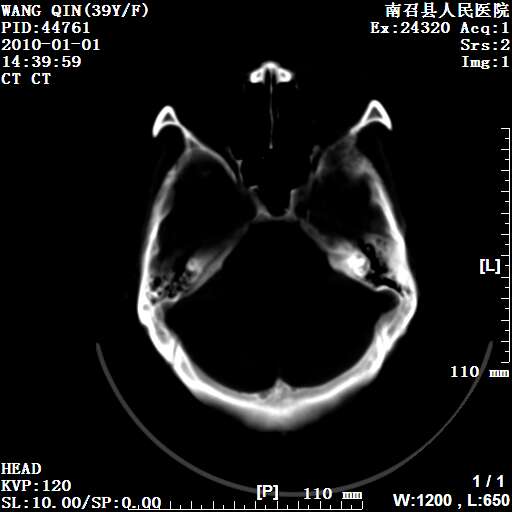

以下是引用随光逐影在2010-1-22 9:03:00的发言:[br]考虑左侧中颅窝(蝶骨翼区)脑膜瘤侵犯蝶骨翼并突入左侧眼眶。

以下是引用水过无痕在2010-1-22 14:55:00的发言:[br]一、定位:颅外占位;二、定性:恶性可能性大;三、组织来源:来源于左侧眼外直肌或其他部位;考虑为:横纹肌肉瘤>转移瘤>脑膜瘤.